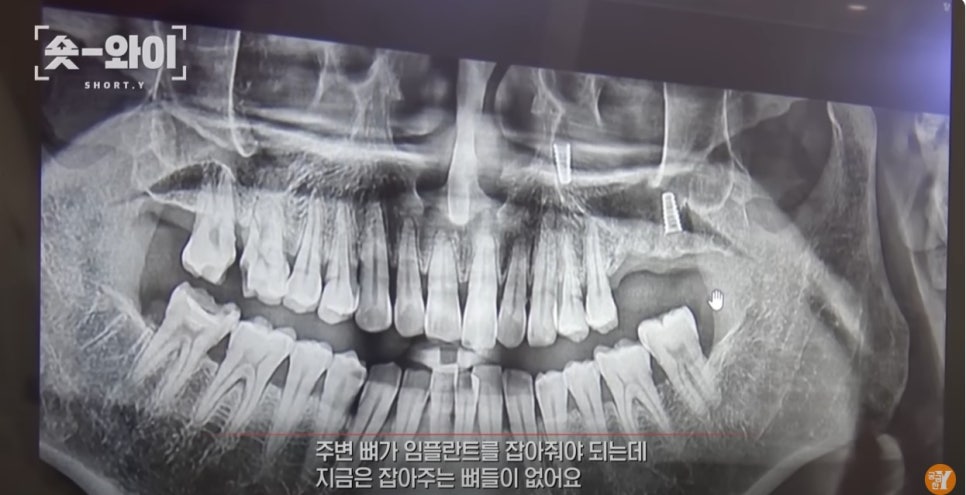

해당내용은 상악동 거상술에 이은 임플란트 식립을 내용으로 인터뷰가 진행되었습니다.

모든 진료의 전후사진을 보고 판단할수는 없지만 의뢰받은 여러케이스들을 살펴보며

진료후 나타나는 현상의 공통점과 치과치료에 대한 예후와 치료 술식에 관한 주제로 인터뷰를 진행했습니다.